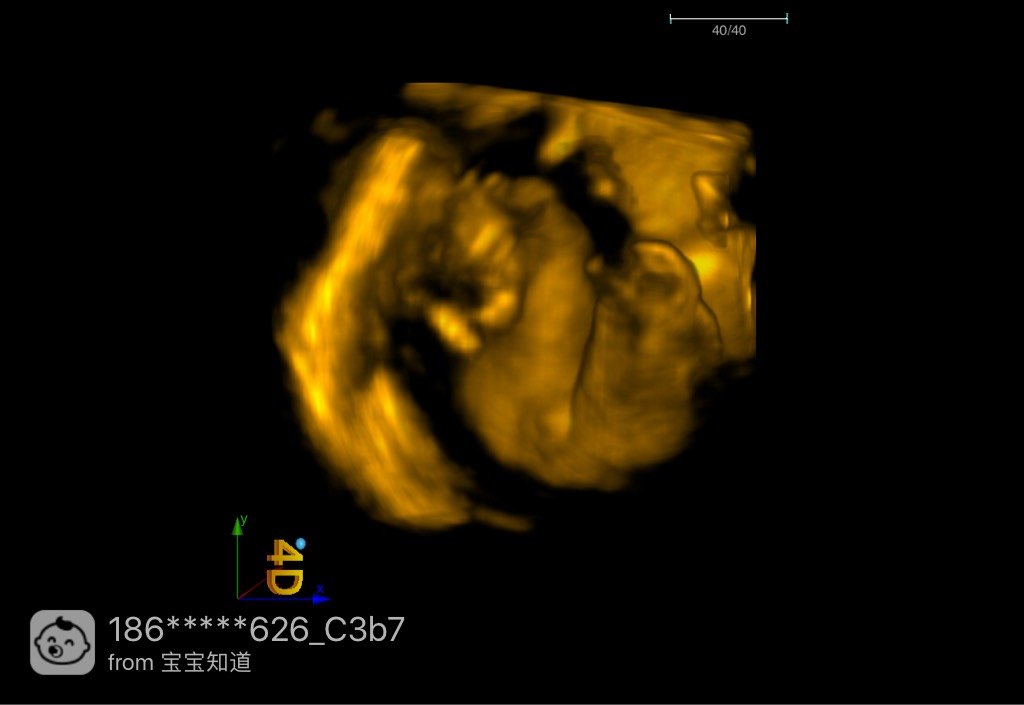

照了四维有会看男女的吗?

四维彩超照完了,关键部位医生也拍了,但是还是锈侨不会看实浅今,有没有会看的团肆宝妈

男宝

24+3周